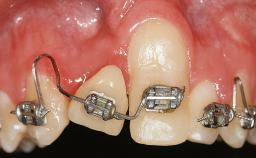

Early Implant Placement, Contour Augmentation, and Autologous Connective-Tissue Graft Using a Tunneling Technique to Replace an Upper Incisor with Generalized Gingival Recession

Variations in soft-tissue volume, evidenced either by an overabundance (Evian and coworkers 1993; Levine and McGuire1997; Dolt and Robbins 1997) or by a deficiency of soft or hard tissue can complicate implant-supported rehabilitations in the esthetic zone (Lorenzana 2008; Lorenzana and coworkers 2009). The present case illustrates the replacement of a failing upper left lateral incisor complicated by generalized severe gingival recession in the esthetic zone.